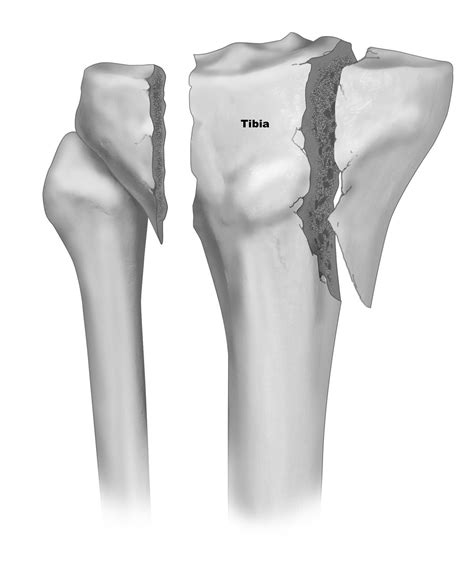

• Tibial Plateau Fractures: These are typically caused by high-energy trauma, such as car accidents or falls from heights. A fracture here disrupts the smooth cartilage surface, potentially leading to post-traumatic arthritis.

Surgical Interventions

When conservative efforts fail or if the medial tibial plateau is displaced significantly by a fracture, surgery becomes necessary. This might involve Open Reduction and Internal Fixation (ORIF) to restore the anatomical alignment of the bone using plates and screws. In advanced cases of osteoarthritis, a partial or total knee replacement may be the only way to restore function and alleviate chronic discomfort.